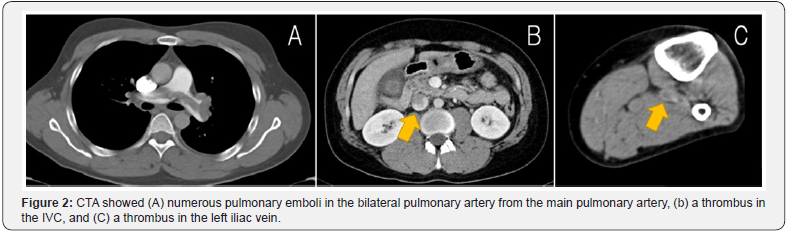

Two weeks postoperatively, his cast was converted into an Achilles tendonitis brace. However, 24 days postoperatively, he presented to the emergency department with sudden severe dyspnea. On examination, his blood pressure was 88/59mmHg, pulse 98/min, and respiratory rate 26/min, with an O2 saturation of 93% in room air. CTA showed numerous pulmonary emboli in the bilateral pulmonary artery from the main pulmonary artery (Figure 2A). CTA also showed a vein thrombus in the IVC (Figure 2B) from the left iliac vein (Figure 2C). There was no thrombus in the right iliac vein. The patient was administered an anticoagulant and IVC filter as treatment for acute PE. The side of the Achilles tendon surgery coinciding with the side of the thrombus strongly suggested the Achilles tendon repair was the cause of PE. One month later, angioplasty revealed the thrombus had disappeared, so the IVC filter was removed. The patient showed a good functional outcome and returned to work at the six-month follow-up.